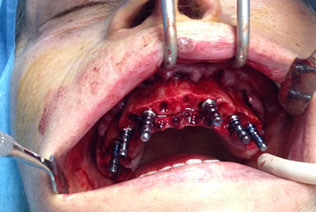

L’implantologia all on 4

è la nuova frontiera della protesi impiantare a carico immediato: consente di eseguire una protesi dentale fissa totale (ovvero che sostituisce tutti i denti di un’arcata, superiore e/o inferiore) con l’inserimento di soli quattro impianti.

L’implantologia all-on-four è stata ideata dal Dr. Malò e prevede l’inserimento strategico di 4  impianti di cui 2 inclinati.

Prima dell’intervento deve essere effettuata la visita clinica del chirurgo odontoiatra e lo studio radiografico dei mascellari che consente di identificare le zone più adatte ad accogliere gli impianti.

Nel caso ci fossero indicazioni al carico immediato il paziente uscirà dallo studio odontoiatrico con un provvisorio fisso che verra’ sostituito da un definitivo dopo qualche mese.

riabilitazione completa su impianti

due casi all on four carico immediato

implantologia con carico immediato su 6 impianti